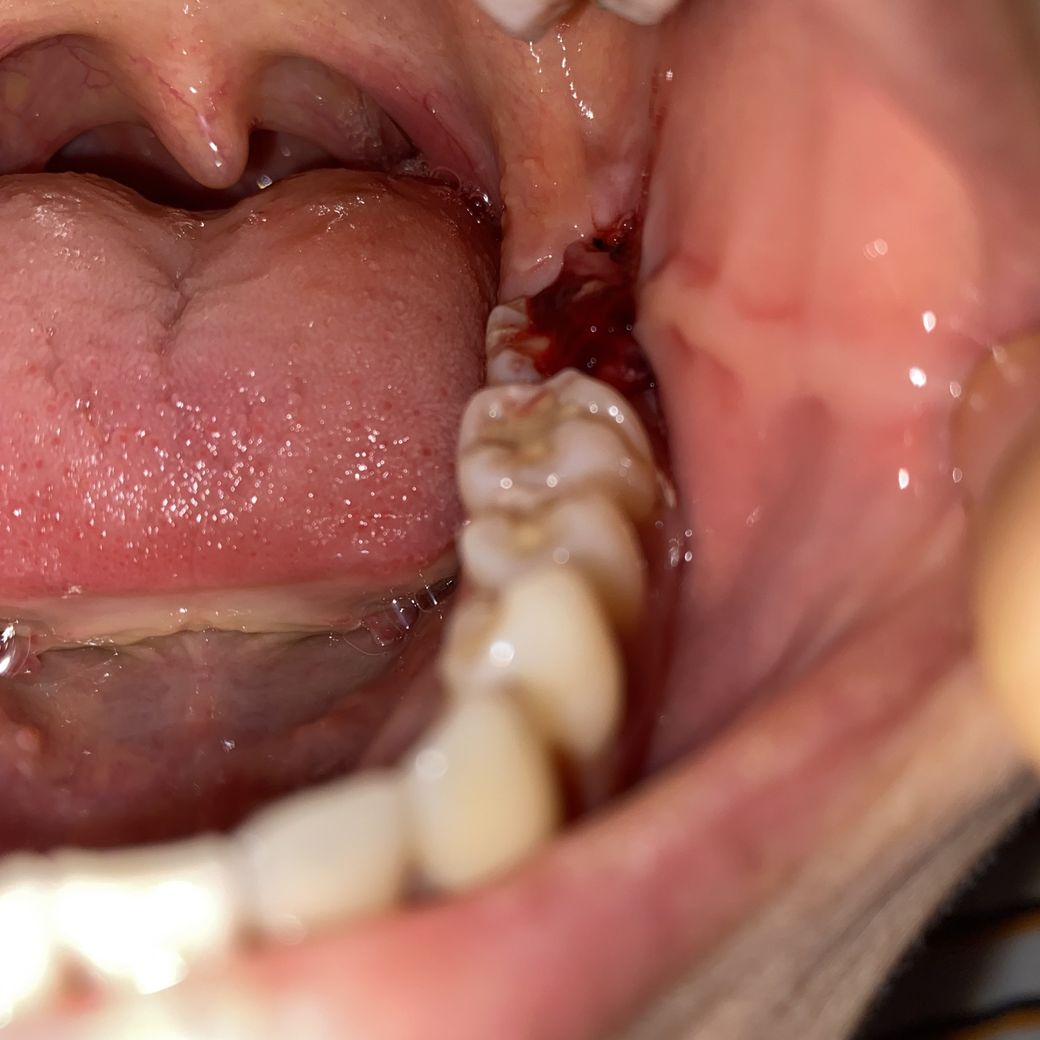

사랑니 제대로 낫고있는게 맞나요?

월요일에 뽑고 지금 5일째입니다.

피맛이 너무 많이나서 보니 피가 나고있는 것 같아서요ㅠㅠ

드라이소켓이 가장 잘 발생한다는데 그런 가능성은 없어보이나요?ㅜ

매복사랑니인데 머리가 약간 나와있다고 했었어요…

질문하신 내용에 대하여 아래와 같이 답변 드립니다.사랑니 발치 이후에 지혈이 잘되고 있지 않아 보입니다. 만약 드라이 소켓이면 발치 이후 2~3일부터 극심한 통증이 나타났을 것입니다. 현재 통증에 대한 증상이 나타나지 않는 것으로 보아 드라이소켓 보다는 지혈이 잘 이루어지지 않았는 것으로 보이며 치과 방문 후 다시 지혈하시길 바랍니다.

질문하신 내용에 대하여 아래와 같이 답변 드립니다.발치후 5일이 되었는데도 사진을 보면 피가 어느정도 나는 것으로 보입니다.

발치와 부위에서 피가나는것인지는 불분명하나, 발치한 치과에 가셔서 확인을 해보시고, 만약 발치부위에서 피가난다면 추가적인 지혈처치가 필요할 수 잇습니다. 감사합니다.